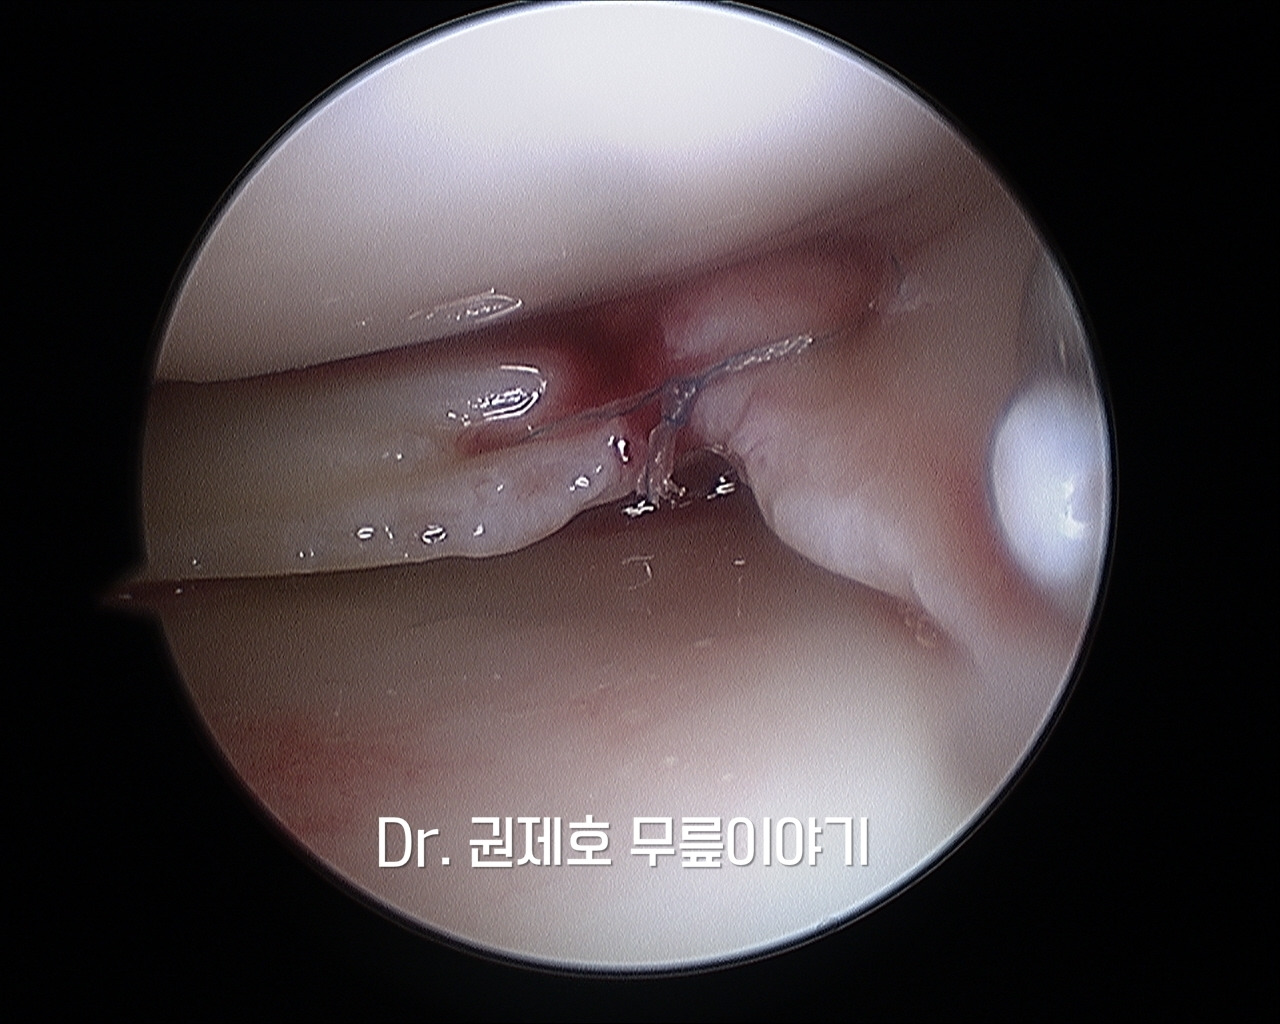

무릎관절경

무릎 관절경을 이용하여 연골판의 모양을 살펴보니 방사형파열이 보이고, 연골판 전체를 가로지르는 파열이 보였다.